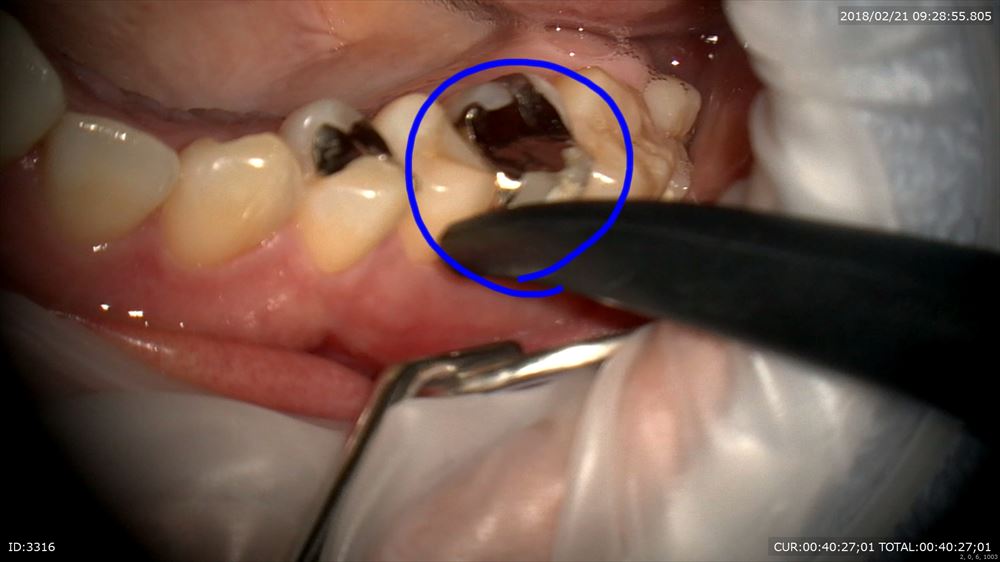

「他院で行った右上の歯が痛い」

神経が腫れて辛そうでした。歯科ドックで原因をお話しし本日精密根管治療スタート

この歯。やはり銀歯虫歯からの細菌侵入。隙間がありますね。

アップ。こんなに。。。

金属を外すと

神経が腫れていました